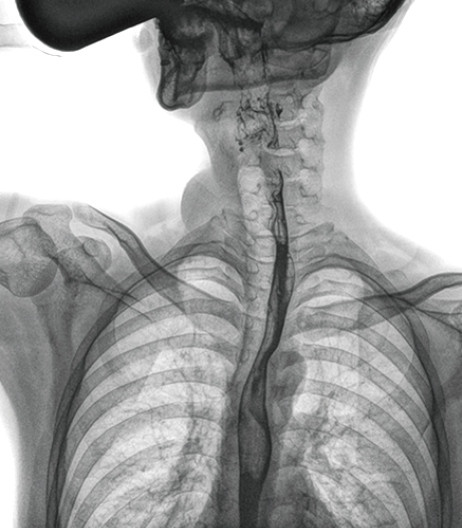

食管造影是食管病變的基本檢查方法,可以發現食管癌的特征性改變——食管粘膜的中斷和破壞,病人常感覺吞咽障礙,此特征在臨床中最常見,也是早期食管癌的典型表現。一般伴隨的特征有管壁充盈缺損、龕影、軟組織塊影、食管腔狹窄等;在透視下還可看到食管壁僵硬、蠕動緩慢等。

動態DR能夠實現大幅面透視,瞬時高清點片等。在食管造影檢查中,由于吞咽鋇劑后,造影劑流速非常快,在一個大幅面上方便觀察食管的病變。瞬時點片,可以實時捕捉到病變部位的影像,從而可以快速做出診斷。普利德多功能動態DR擁有17×17英寸超大視野,一次曝光即可顯示整個食管,更方便觀察食管的病變,確定病變的范圍,對診斷和治療有重要參考價值。

動態DR可以動態觀察管壁蠕動是否僵硬,以鑒別良、惡性狹窄,不但在透視過程中,可實時高清點片,實現毫秒級動靜態圖像切換,快速捕捉病變部位的影像,成像清晰而迅速,盡可能減少食管功能性障礙患者因吞咽困難而忍受痛苦的時間,同時提高醫生做出正確診斷的效率,還能實時保存視頻影像,反復觀察、分析,明確病變范圍,對手術有重要的指導意義。

與過去的數字胃腸機比較,動態DR圖像分辨率高,對食管的全景觀察,局部粘膜破壞、中斷,管腔狹窄以及病灶范圍的顯示清晰度明顯更優。